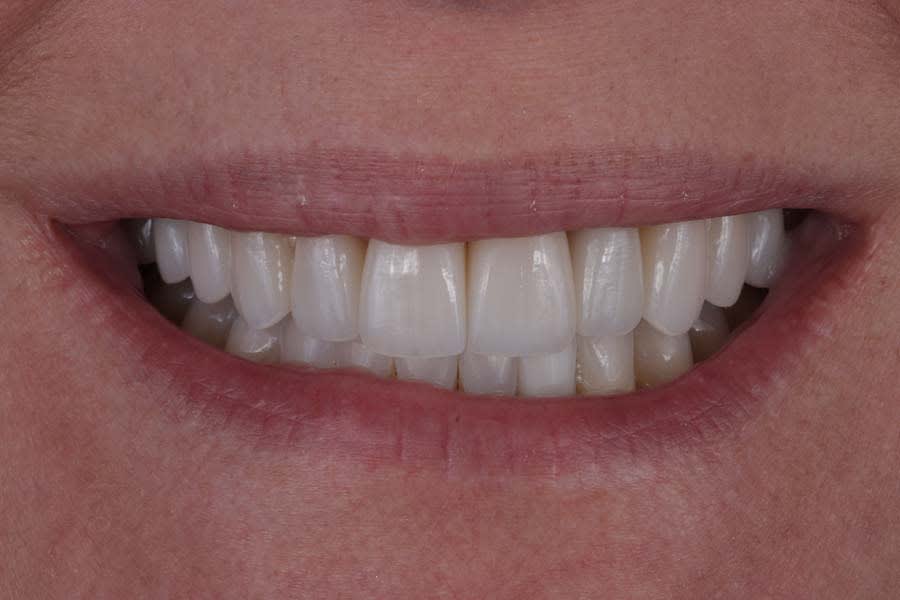

Post-treatment photographs demonstrating the successful outcome of the case are shown in Figure 15 through Figure 19.

Clear aligners (Invisalign) were used to correct gingival margin discrepancies, reduce the black triangle between teeth Nos. 9 and 10, and optimize occlusal forces by uprighting posterior teeth. This orthodontic phase, paired with airway considerations, enabled functional and esthetic improvements without compromising tongue space. Establishing adapted centric posture via deprogramming created a stable occlusal scheme, thereby minimizing risks of further attrition or restoration failure. Lithium-disilicate crowns and resin infiltration restored function and delivered a natural, esthetic smile, with precise laboratory collaboration ensuring accurate shade and contour.

This case exemplifies the transformative potential of a structured, systematic approach in transitioning a patient from single-tooth dentistry to comprehensive care. By addressing biomechanical, functional, periodontal, and dentofacial risks through integrated orthodontic and restorative treatments, the treatment achieved a stable, functional occlusion and an esthetically pleasing smile. The use of clear aligners, precise occlusal management, and cohesive restorations resolved immediate concerns and reduced long-term risks. Since treatment completion in early 2023, the stability of the restorations and the patient’s satisfaction have underscored the success of this approach in delivering lasting functional and esthetic outcomes.